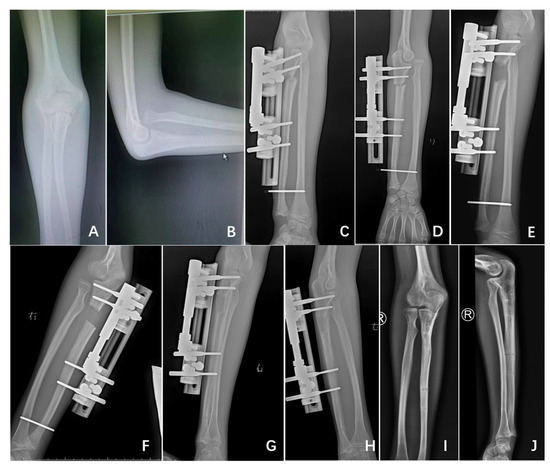

- Lengthening distance of the ulna (DU): the distance, in millimetres (mm), between the proximal and distal fragments of the fractured ulna (Figure 3); and

- Angulation of the ulna (AU): the angle, in degrees, between the line passing at the level of posterior cortex of the proximal and the distal fragment of the fractured ulna (Figure 3);